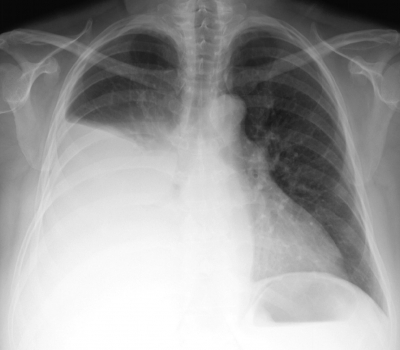

身長 151 cm、体重 70 kg。体温 36.8 ℃。脈拍 92/分、整。血圧 130/102 mmHg。呼吸数 18/分。SpO2 94 %(room air)。呼吸困難の原因は胸水貯留であると考え、入院の上、胸腔穿刺を行い胸水を排液した。呼吸困難は一時的に改善したが、 穿刺1時間後に強い呼吸困難と泡沫状の喀痰がみられ、SpO2 92 %(鼻カニューラ2L/分 酸素投与下)となった。 穿刺2時間後、症状はさらに悪化し、SpO2 85 %(マスク8L/分 酸素投与下)となったため気管挿管を行った。来院時と胸腔穿刺1時間後の胸部エックス線写真と胸部CTとを示す。

来院時